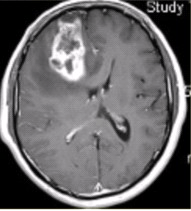

患者女,68岁。头痛、恶心2周,加重2d。头CT显示如下图。

可能的诊断是(提示头颅CT增强及CT灌注成像(脑血流量及表面渗透值明显升高)显示如下图。)()

A.病变与脑实质边界不清,跨越大脑镰提示病变位于轴内

B.病变密度较高,提示内部伴发出血

C.病变邻近颅骨可见骨质肥厚,支持病变位于轴外

D.病变形态不规则,周围水肿明显,支持病变位于轴外

E.为进一步明确诊断,需增强检查

F.CT平扫可以评价病变与硬脑膜的关系

CT、MR支持病变位于轴外的征象是()

A.病变边界清晰,形态不规则,呈分叶状

B.病变邻近的蛛网膜下腔增宽

C.病变呈等T1等T2信号影

D.大脑镰可见明显强化,CBV及PS明显升高

E.病变周围水肿明显

F.病变占位效应明显

可能的诊断为(提示进一步MRI检查显示如下图。)()

A.脑膜瘤